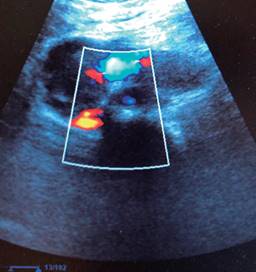

El efecto piezoeléctrico, descubierto por Jaques y Pierre Curie en 1881, consiste en que cuando a los cristales de cuarzo se les aplica determinado voltaje, generan ondas de presión sónica que rebotan en las superficies cercanas y son recibidas como ecos por los mismos cristales. La capacidad de estos cristales para generar y recibir ondas de presión en el rango de frecuencias de megahercios permitió el desarrollo de la tecnología de transductores moderna. Todo transductor sonográfico usado en la medicina clínica contiene dichos cristales. La frecuencia de sonido emitida es demasiado alta para percibirse por el oído humano. Dichas ondas emitidas y recibidas como ecos, son ordenadas por un procesador en pixeles que genera imágenes susceptibles de interpretación clínica. En 1820 Jean-Daniel Colladon confirmó que la velocidad del sonido varía según el medio en el que se disperse, siendo más lenta en un medio acuoso que fuera del mismo. Por lo tanto, tejidos (o cavidades) con diferentes porcentajes de densidad acuosa resistirán de manera peculiar el paso de la señal sonográfica (hígado, hueso, tendón, sangre). Ese fenómeno se conoce como impedancia. Por último, la descripción de Christian A Doppler, en 1842, del efecto que lleva su nombre. Imaginémonos un tren que se acerca haciendo sonar su bocina, cuando un objeto que produce sonido se mueve hacia un observador, la frecuencia de sonido recibida es más alta que la frecuencia emitida; cuando el productor de sonido y el observador están en el mismo punto, las frecuencias emitidas y recibidas son idénticas; y cuando el productor de sonido se aleja de un observador, la frecuencia recibida es más baja que la frecuencia emitida. Los equipos dotados de Doppler color, reproducen este fenómeno al traducir las imágenes de fluidos que se desplazan (sangre circulante), ya sea acercándose (color rojo) o alejándose (color azul) del transductor (Interesados en la historia y los fundamentos de la física del ultrasonido pueden consultar este interesante documento).10 En esencia, la máquina de ultrasonido consta de dos partes principales, el transductor y el procesador (aunque algunos novedosos ultrasonidos portátiles contienen el procesador dentro del transductor) y basta con conectarlos a una Tableta o un teléfono inteligente que cuente con la aplicación de la marca, y estos funcionan como la pantalla o monitor del mismo (Figura 1). El transductor tiene dos funciones principales: primero, generar una onda de sonido de alta frecuencia (actúa como emisor) y, segundo, recibir una onda de sonido reflejada (actúa como receptor del eco que la onda emitida generó). El procesador, ubicado dentro de la unidad de ultrasonido, toma estas señales entrantes y las convierte en una imagen útil. Las ondas emitidas son alteradas por la impedancia tisular, es decir, la resistencia que oponen los tejidos al paso se la señal sonográfica, a mayor impedancia mayor rebote de la señal o, lo que es lo mismo, mayor ecogenicidad. Una estructura dura (un lito, el hueso) resisten completamente el paso de la señal, ésta rebota y genera una imagen blanca brillante (imagen hiperecoica), (el hueso o el lito donde chocó la señal), seguida de una sombra obscura, es decir, la llamada sombra acústica posterior (a donde la señal no llegó en absoluto, de ahí la obscuridad). Por el contrario, los tejidos blandos (tendón, músculo, hígado, riñón, tiroides, pared intestinal, un tumor) oponen cada uno variedades propias de impedancia, generando imágenes en contraste de grises sin sombra acústica que se traducen en cada uno de ellos en una imagen sonográfica característica, como por ejemplo el contraste que tiene la ecogenicidad entre corteza y médula renales.11-13 Un objeto líquido rodeado de una pared de tejido blando (la vesícula biliar, un quiste, un vaso sanguíneo) permite el paso franco de la señal, generando una imagen obscura (anecoica), rodeada de la pared que se aprecia en color blanco que persiste en la parte inferior de la pantalla, fenómeno característico de la escasa impedancia de los medios líquidos conocido como “reforzamiento posterior”. Órganos o estructuras compuestas por tejido blando como el hígado y el riñón, o una masa tumoral, que son vecinos próximos o continentes de vasos sanguíneos, reproducen una señal ultrasonográfica que muestra claramente el parénquima y el vaso (vena porta, vasos renales, vena cava inferior, venas suprahepáticas, conductos biliares, sistema colector). Con la adición del Doppler color, dentro de una masa sólida (hígado, tumor) puede confirmarse que es atravesada por un vaso sanguíneo pulsátil, y todas estas estructuras pueden medirse en cuanto a diámetro, volumen, pulsaciones, etcétera. Una vesícula biliar ocupada por cálculos mostrará en su interior imágenes blancas (hiperecoicas) que, al ser duras, generan una imagen de contorno hiperecoico (blanco) y proyectan una sombra acústica posterior. La pared abdominal, constituida por tejidos blandos con distinta impedancia, permite diferenciar músculo, tendones, aponeurosis, grasa, y fenómenos extraños como una solución de continuidad con la emergencia en la maniobra de Valsalva de un tejido blando, lo que se traduce en el diagnóstico objetivo de una hernia de pared. Las colecciones líquidas patológicas (sangre, pus, líquido seroso) pueden identificarse, como puede ser la presencia de una banda anecoica entre el hígado y el riñón derecho (espacio de Morrison), correspondiente a sangre o líquido libre intraperitoneal. Los equipos actuales de ultrasonido se fabrican con un refinamiento técnico tal que permite una resolución notable, facilitando la exploración de todo tejido, trátese de tendón, espacios articulares, músculo, globo ocular, o cavidades torácica, pericárdica o abdominal y las imágenes generadas pueden ser medidas, fotografiadas o videograbadas, en tiempo real y es posible compartir esos hallazgos vía internet en segundos. ¿Quién puede ser capaz de creer que esta herramienta no debe estar en manos del clínico que busca respuestas objetivas, concretas, medibles y en forma inmediata? Otros principios de ultrasonido que afectan nuestra imagen incluyen absorción, dispersión y ángulo de reflexión, superan los alcances del presente artículo, pero pueden consultarse en los artículos referidos.14

El cirujano general aborda particularmente problemas clínicos que incluyen el aparato digestivo, el cuello, la pared abdominal y los trastornos del sistema circulatorio y el tórax. Un artículo publicado en 2008, por Lindelius,15 demostró que la implementación del ultrasonido por parte del cirujano general en casos de dolor abdominal agudo incrementó en 7.9% la precisión diagnóstica. En la consulta cotidiana de la especialidad, incorporar el rastreo sonográfico al área explorada agrega minutos al examen clínico que aportan datos de notable valor por la objetividad y precisión. El abdomen suele ser el sitio que los cirujanos generales exploramos con más frecuencia. Es posible en una consulta cotidiana hacer todo el protocolo de ultrasonido de abdomen superior en minutos, que incluye ambos cuadrantes superiores y los flancos, pudiendo observar el hígado, la vesícula y los conductos biliares, ambos riñones, el bazo, parte del páncreas y, con ayuda del Doppler color, los principales vasos de la región como la vena cava inferior, la aorta abdominal, la vena porta, los vasos esplénicos y la arteria hepática. Puede haber limitantes como el contenido gástrico, el nivel de llenado de la vesícula biliar o la constitución del paciente y su capacidad de cooperar con el estudio. Pero con la práctica cotidiana, se adquieren las destrezas y el refinamiento suficientes para lograr, con la experiencia acumulada, producir imágenes de relevancia diagnostica inmediata. En la fase de entrenamiento, contrastar nuestros hallazgos con información disponible en la red, con los colegas imagenólogos, o cirujanos ya experimentados en ecografía, permitirá la retroalimentación y la tutoría esenciales de toda curva de aprendizaje. Tradicionalmente se consideraba que aquellos órganos que contienen una mezcla de líquido y gas (intestino, estómago) no son valorables por ultrasonido, el gas produce un efecto rarefacción, ya que no comprime las ondas como un tejido solido o un medio líquido, la señales entonces se dispersan impidiendo que regresen como ecos y permitan al procesador formar una imagen congruente con el órgano explorado. Sin embargo, cuando esta condición cambia como consecuencia de un estado patológico, es posible identificar el contenido intestinal o el gástrico y darnos una idea más aproximada de lo que realmente está ocurriendo en ese abdomen. Podemos, por ejemplo, saber si un estómago está lleno de líquido, o si el intestino contiene residuo sólido, líquido o gaseoso. Los equipos actuales pueden incluso ver en detalle la pared intestinal cuando ésta esté dilatada. Se puede distinguir cuando el colon está ocupado de líquido a nivel del flanco izquierdo como podría ser en una colitis amebiana o en una oclusión intestinal,16 donde se observa dilatación del intestino delgado ≥ 25 mm, el peristaltismo anormal, la presencia de líquido libre intraperitoneal y el edema de la pared intestinal (Figura 2). En casos de dolor abdominal agudo, el ultrasonido puede, en forma inmediata, permitir diagnósticos diferenciales como el hallazgo de una dilatación pielocalicial por nefrolitiasis (Figura 3), o un aneurisma de la aorta abdominal (Figura 4). Un estudio prospectivo realizado en Irvine, California,17 encontró que la a capacidad diagnóstica del médico de primer contacto practicando el ultrasonido para detectar una colelitiasis tiene una especificidad de 87% y una sensibilidad de 82%, mientras que la prueba de ultrasonografía realizada por radiología tuvo sensibilidad de 83% y una especificidad de 86%. Es decir, que, ahorrando tiempo al paciente, el diagnóstico de colelitiasis es factible agregando unos minutos al examen físico inicial. En casos de apendicitis, el método diagnostico considerado como el estándar de oro es la tomografía axial computarizada (TAC). Sin embargo, tiene inconvenientes como su disponibilidad, su costo, el riesgo de radiación en niños y pacientes embarazadas. En tales situaciones, sobre todo en niños, sexo femenino o pacientes delgados, el ultrasonido es una poderosa herramienta que complementa el examen clínico inicial. Las ventajas del ultrasonido frente a la tomografía serian su ubicuidad (ya está en la sala de emergencias), el bajo costo, la ausencia de radiación y el diagnóstico diferencial con causas ginecológicas o genitourinarias de dolor. En apendicitis, la sensibilidad y especificidad de la TAC es de 99.4% y 80.0%, respectivamente. Para el ultrasonido, la sensibilidad diagnóstica es de 83% y la especificidad de 90%. La tasa de apendicectomía negativa es ligeramente mayor en el grupo de TAC que en el del ultrasonido, es decir, 7.1% (3/42) (TAC) en comparación con 4.67% (5/107) (ultrasonido). Hay que recalcar que el ultrasonido es operador dependiente. La experiencia y la calidad del equipo juegan un papel importante.18 La apendicitis tiene varios hallazgos característicos, como la pared edematosa y el aumento de grosor general. Se toman para criterios de positividad una estructura tubular aperistáltica no compresible que mide más de 6 mm de diámetro en el cuadrante inferior derecho (Figura 5).19-21